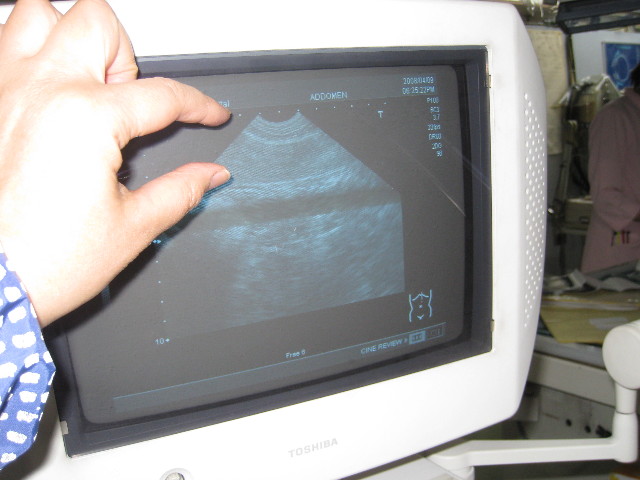

これは脾臓(指先の範囲の他と違って写っている層)

脾臓は大きいけど大丈夫だって。